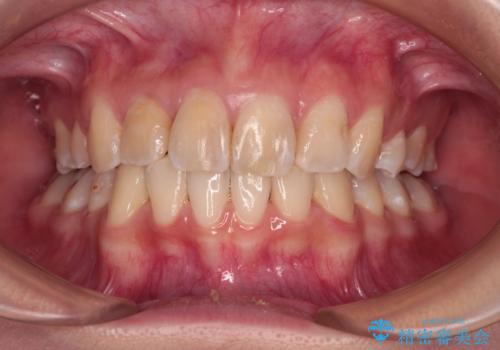

- 1本飛び出した前歯を治したいとのことで来院された患者様です。

歯列全体の拡大とIPR(歯と歯の間を削る)によってデコボコが解消するようにし、さらにゴムかけを活用して右側の咬み合わせ位置を変えるように設計し、インビザラインにより治療を行うこととしました。